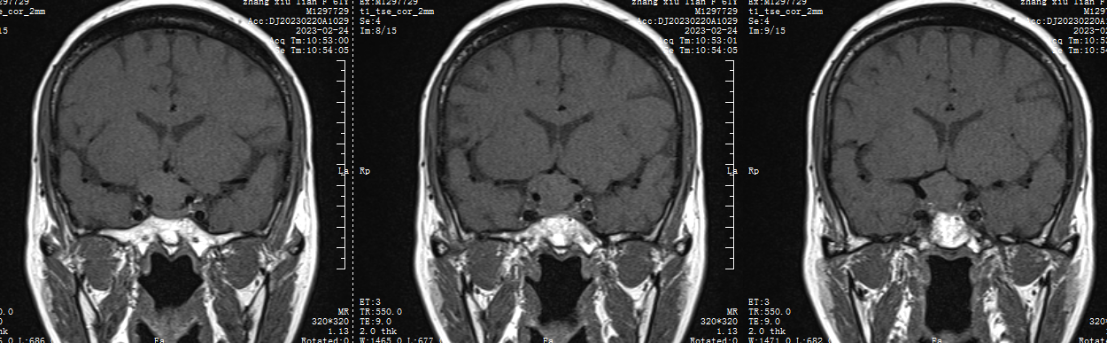

1.患者张XX,女,61岁,以“头晕2天”为主诉入院。

5.辅助检查:垂体激素水平正常

二 术前检查及会诊

鞍结节脑膜瘤(tuberculumsellaemeningioma TSMs)仅占颅内脑膜瘤的4%~10%。鞍结节脑膜瘤沿脑膜向周围生长,向前可达眶尖,向后可达斜坡及小脑幕,向外沿中颅窝底扩展,向内可累及鞍内垂体腺。常最早侵犯视神经,多以视力障碍为首发症状,产生颅高压为引起头痛、恶心、呕吐,侵犯垂体会出现垂体功能障碍相应症状。

鞍结节脑膜瘤(TSMs)的处理方案包括观察、显微手术切除和/或立体定向放射外科治疗。患者往往是在肿瘤侵犯视器造成视觉损害后才得以诊断,此时必须解除病变的占位效应,因此放射外科治疗或观察就显得不太合适,所以对于症状性患者最好采取显微外科切除的措施。